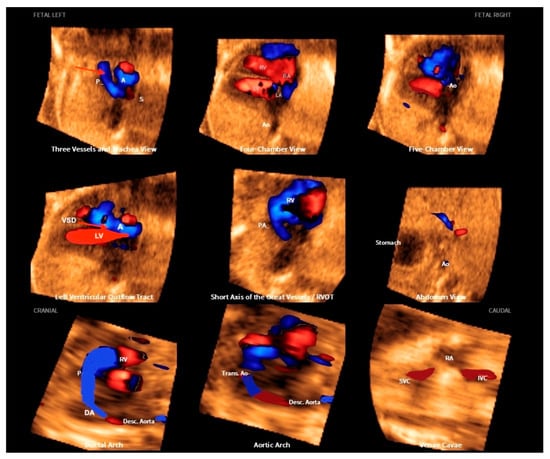

Figure 18.

Fetal Intelligent Navigation Echocardiography (FINE), also known as “5D Heart”, in a case of tetralogy of Fallot. Note the small pulmonary artery in the three vessels and trachea view and the overriding of the aorta in the left ventricle outflow tract view (red arrows). A or Ao, aorta; P, pulmonary artery; LV, left ventricle; LA, left atrium; LV, left ventricle; RV, right ventricle; VSD, ventricular septal defect; DA, ductus arteriosus; SVC or S, superior vena cava; IVC, inferior vena cava; Trans. Ao, transverse aorta; Desc. Aorta, descending aorta; RVOT, right ventricle outflow tract.

For the diagnosis of tetralogy of Fallot, the outflow tract views are critical, and advanced imaging techniques will improve the accuracy and timing of the ultrasound examination, as in classic tetralogy of Fallot, the image of the fetal heart in the 4C view is normal [34,51]. Tetralogy of Fallot with subpulmonary stenosis is the classic form of this CHD, while the extreme form is pulmonary atresia. There is also a rare form of tetralogy of Fallot in which the pulmonary valve is absent [52,53].

The standard 4C view using 2D ultrasound is generally normal in the classic forms of tetralogy of Fallot, where the evaluation of the outflow tract views is critical. Advanced technologies such as 5D Heart can help to reduce the time of the scan examination by allowing the automatic reconstruction of the nine echocardiographic views. Therefore, in the classical forms of tetralogy of Fallot, this diagnosis becomes easier by drawing attention to the small pulmonary artery in the three vessels and trachea view and the overring of the aorta in the left ventricle outflow tract view [51,52]. In extreme cases, the presence of retrograde flow from the ductus arteriosus to the pulmonary artery confirms the atresia, which can be easily detected with advanced technologies (Figure 19). Conversely, in the forms of tetralogy of Fallot in which the pulmonary valve is absent, the right and left pulmonary arteries are enlarged (Figure 20) [53].